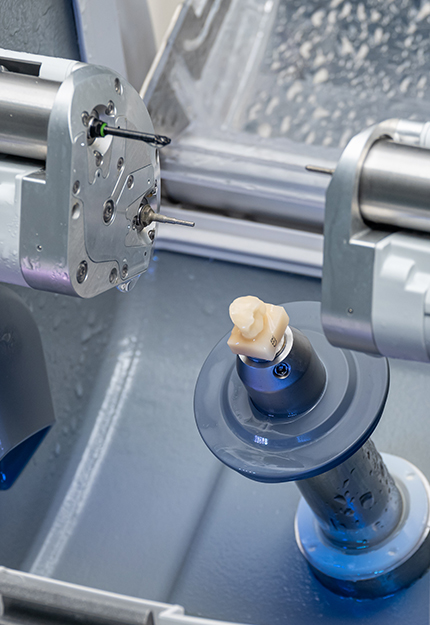

원내 기공ㆍ디지털 치과

진료 시스템

원내 기공과 디지털 분석 시스템을 바탕으로

원내 기공과 디지털 분석 시스템을 바탕으로

CT·CAD/CAM·3D 스캔 기반의 정밀 시스템으로

치과의사와 기공사가 만드는 1:1 맞춤 보철 - READ MORE